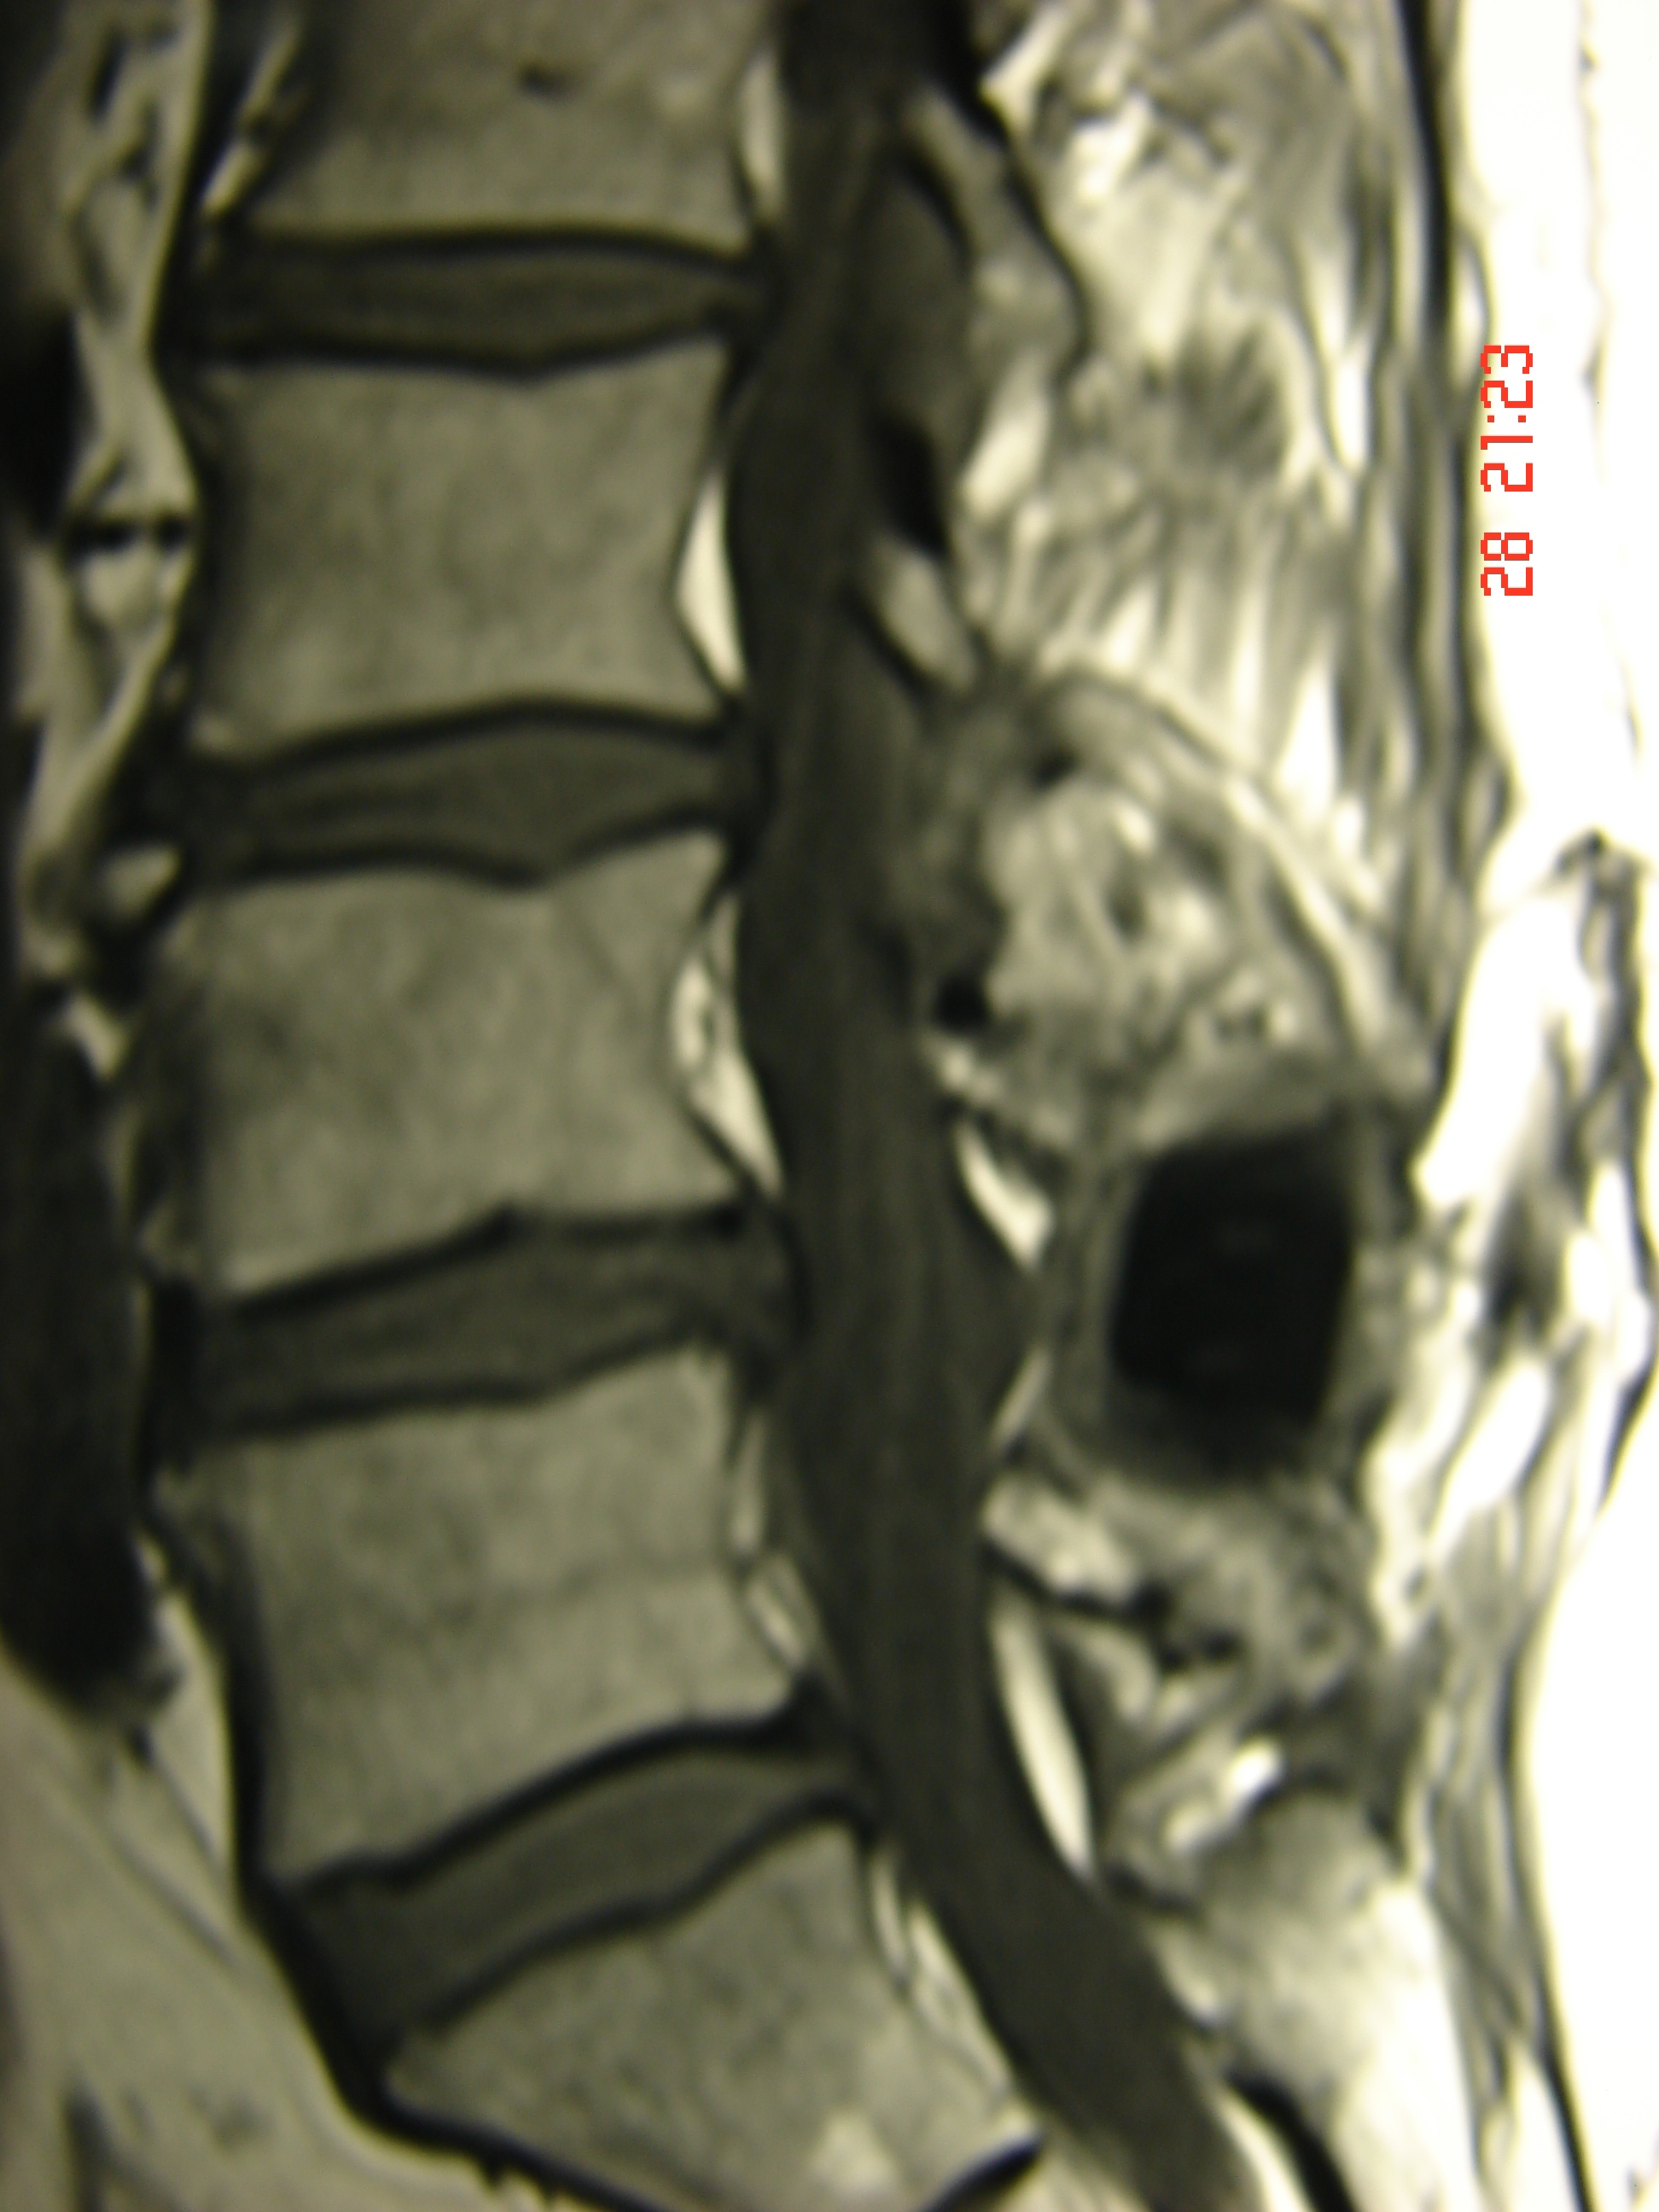

Εικόνα 2: Μαγνητική Τομογραφία (Ο.Μ.Σ.Σ.) εγκαρσία (axial) λήψη

Λόγω της παραμονής των συμπτωμάτων του, τα οποία συνίστατο σε πόνο εντοπιζόμενο στην (Ο.Μ.Σ.Σ.) ο οποίος αυξανόταν καθ’ όλες τις δραστηριότητές του ο πάσχων αποφάσισε να υποβληθεί σε περαιτέρω χειρουργική αντιμετώπιση του προβλήματός του, δεδομένου ότι η συντηρητική αγωγή (φυσιοθεραπεία και φάρμακα) που ακολούθησε για μακρύ χρονικό διάστημα δεν απέδωσε.

Η χειρουργική επέμβαση συνίστατο στη διαδερμική σταθεροποίηση της προβληματικής περιοχής της Ο.Μ.Σ.Σ. με σύστημα κοχλιών και ράβδων.